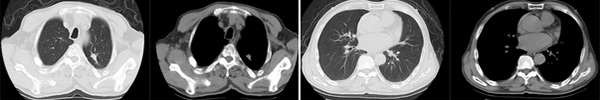

治疗前(2020年6月)

治疗5年(2025年6月)